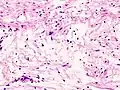

| Micrograph of a schwannoma showing both a cellular Antoni A area (top) and a loose paucicellular Antoni B area (bottom). HE stain. | |